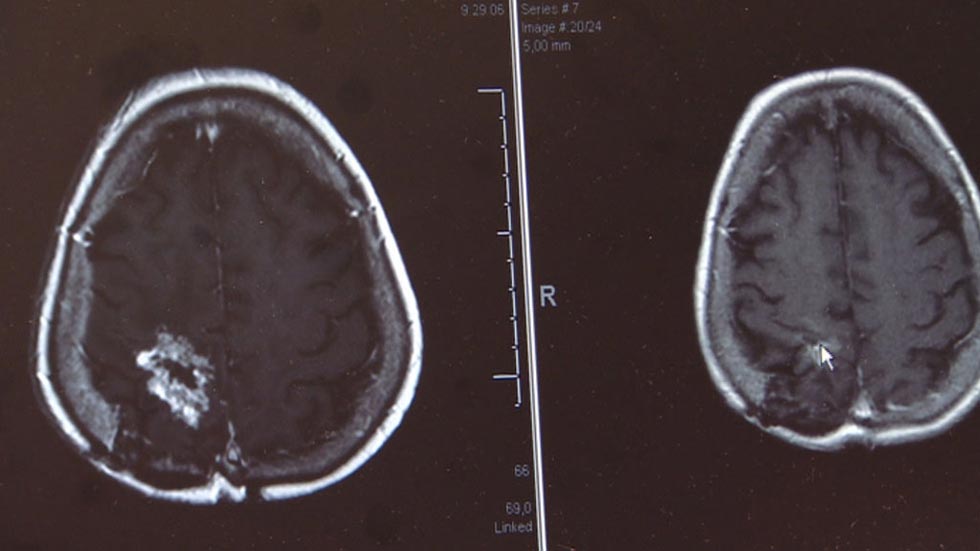

Un estudio español ha demostrado la eficacia de un fármaco contra los glioblastomas, el segundo tumor más agresivo tras el de páncreas y que afecta a uno de cada 100 mil habitantes. En algunos casos, el tratamiento logró reducir el tumor hasta un 85%.